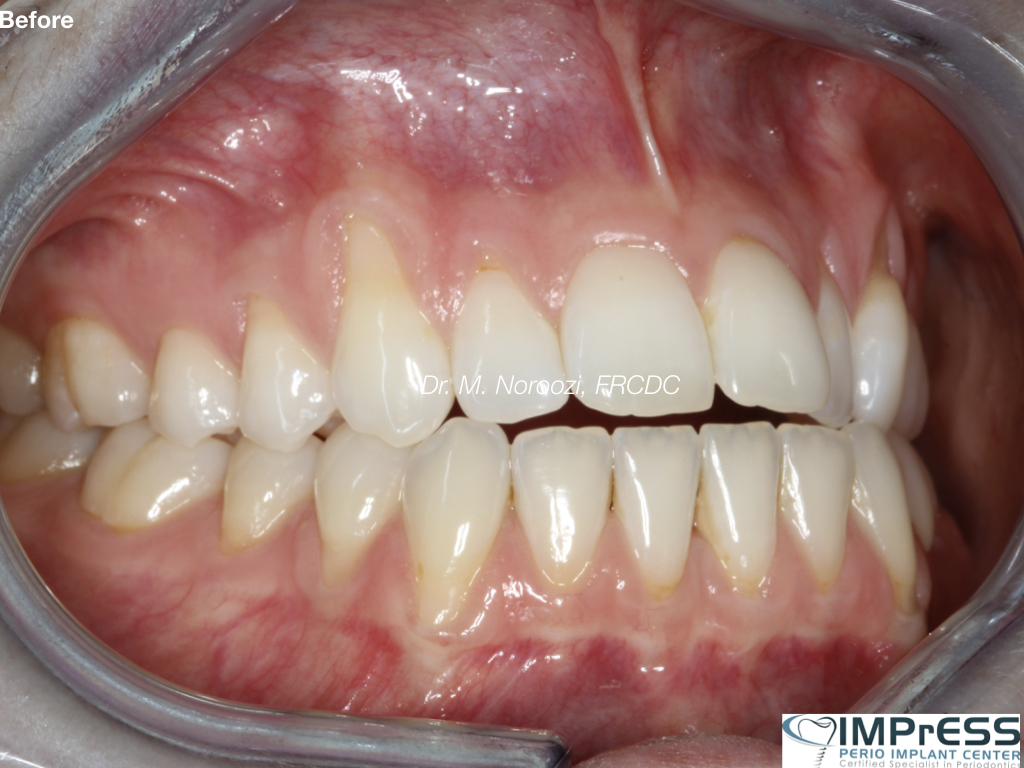

Connective Tissue Gingival Grafting for Gingival Recession